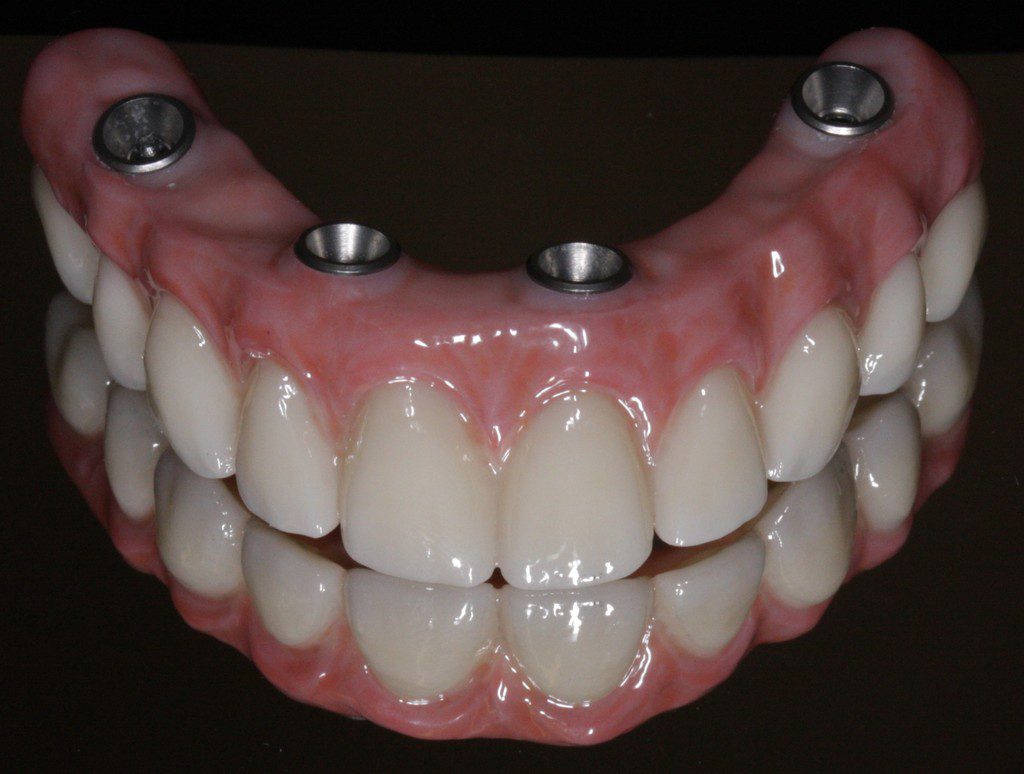

All-on-4 Implant Fixed Bridge

The All-on-4 procedure is a dental implant operation, but instead of placing tooth implants in the gums on an individual basis, this allows for four teeth – more commonly known as a bridge – to be placed in the mouth. In All-on-4 procedures, we place a minimum of four dental implants in each arch. Each arch receives a long bridge of 10 to 14 teeth, depending on the available bone.

Identifying trouble spots within the bone is done using our 3D Cone Beam Scanner. With thorough treatment planning and pre-surgical lab work, patients receive their teeth on the day of surgery. Yes! Patients walk out of the surgery with their teeth. Our patients never have to live a day without teeth. After three to four months of healing, a new and final bridge will be fabricated. An annual visit to our Katy dentist office is required in order to remove the fixed bridge and thoroughly clean it. Aside from that, the only maintenance required is what is common with natural teeth: brushing, flossing, and rinsing.